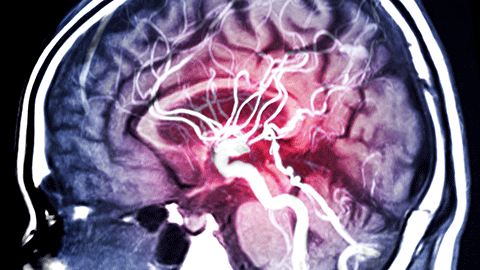

A man has a stroke at age 35. He fully recovers, but is put on a lifelong prescription of anticoagulants. What is going on, and will he ever be able to receive the deep massage he wants? In this episode, Ruth looks at a common anomaly called patent foramen ovale. We discuss its connection to cryptogenic stroke (and we even dive into migraine for a hot second). Finally, we talk about the safety of massage therapy for clients taking anticoagulant drugs.

A client recovering from a stroke seems to have given up on getting better. His massage therapist would like to help, but what can they do? Pathology educator Ruth Werner dives into an “I have a client who ...” story with a description of stroke, how it affects function, and the role of massage therapy in this context.